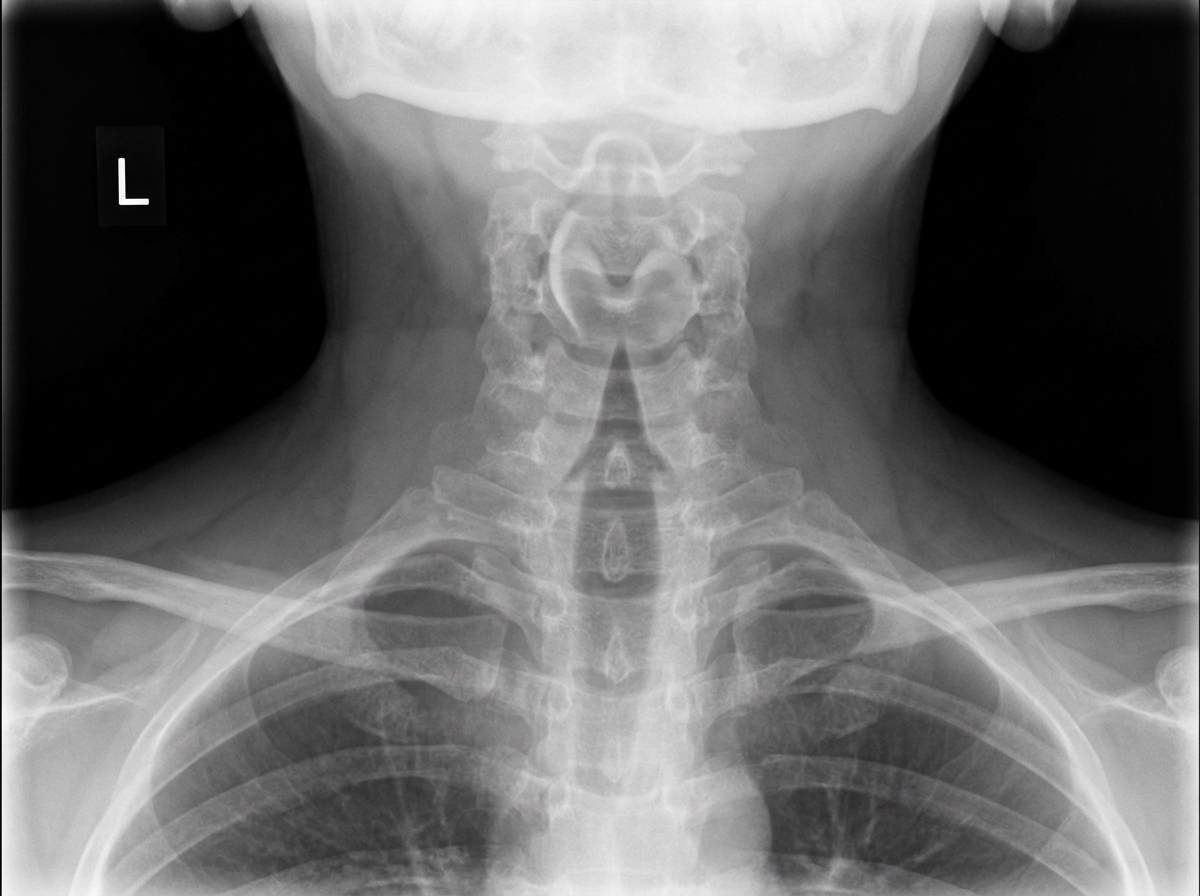

A child presents with fever, stridor, and barking cough. An X-ray is provided below. Which of the following is true about the patient?

Explanation: ***Symptoms are predominantly caused by involvement of the subglottis.*** - The **barking cough** and **stridor** are characteristic of **croup**, which primarily affects the **subglottic area** causing narrowing below the vocal cords. - The **steeple sign** on X-ray (narrowing of the subglottic airway) confirms subglottic involvement typical of croup. *Antibiotics should be started immediately.* - Croup is typically caused by **viral infections** (most commonly **parainfluenza virus**), making antibiotics ineffective. - Treatment focuses on **supportive care**, **corticosteroids**, and **cool mist therapy** rather than antibiotics. *The X-ray is showing the thumb sign.* - The **thumb sign** is characteristic of **epiglottitis**, showing an enlarged epiglottis on lateral neck X-ray. - Croup shows the **steeple sign** (subglottic narrowing), not the thumb sign. *The condition is caused by H. influenzae b.* - **H. influenzae type b** is the classic cause of **epiglottitis**, not croup. - Croup is predominantly caused by **viral pathogens**, especially **parainfluenza viruses** types 1 and 3.